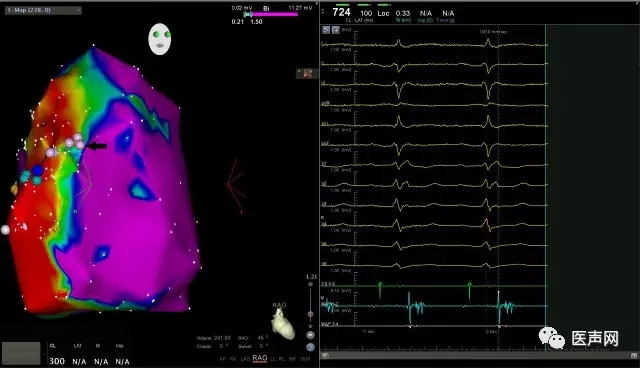

由于患者平时发作频繁,上台后很容易诱发室速,心动过速激动标测发现室速起源部位在三尖瓣环附近,欧阳教授表示很多ARVC的室速都是集中在三尖瓣环周围,该患者也是符合经典情况。消融的重点:一是消除晚点位。消融时找到室速的出口,在出口附近进行拖带,我们找到一个舒张中期非常好的电位,在该电位放电几次后,室速顺利终止,再对心室局部异常心肌内的晚点位进行消融。二是确保无法诱发室速。我们用多种方法,包括异丙酸诱发、心室刺激,均不能诱发室速,消融成功。

欧阳教授指出,因为ARVC起源为心外膜的病变心肌,即心外膜心肌细胞被脂肪组织所代替,随着病情进展,才会逐渐延伸到心内膜,所以很多处于病情初期的患者,进行心内膜标测时,心内膜电压是正常的。

所以这个患者我们考虑到这种情况,请欧阳教授给我们演示一个心外膜的消融标测,该患者心内膜标测时,在三尖瓣环附近就能够找到大片的低电压区,在低电压区内也找到了晚点位,并且能够很好的拖带,在心内膜就能够成功消融。最后,欧阳教授也提到,很多ARVC并不是一定要在在心外膜消融,在心内膜也可以成功消融,因为心外膜三尖瓣环附近是房室沟,冠脉动脉在里面走形,而且往往有很厚的脂肪垫,有时消融会比较困难,反而心内膜会比被心外膜消融成功率更加高一些。